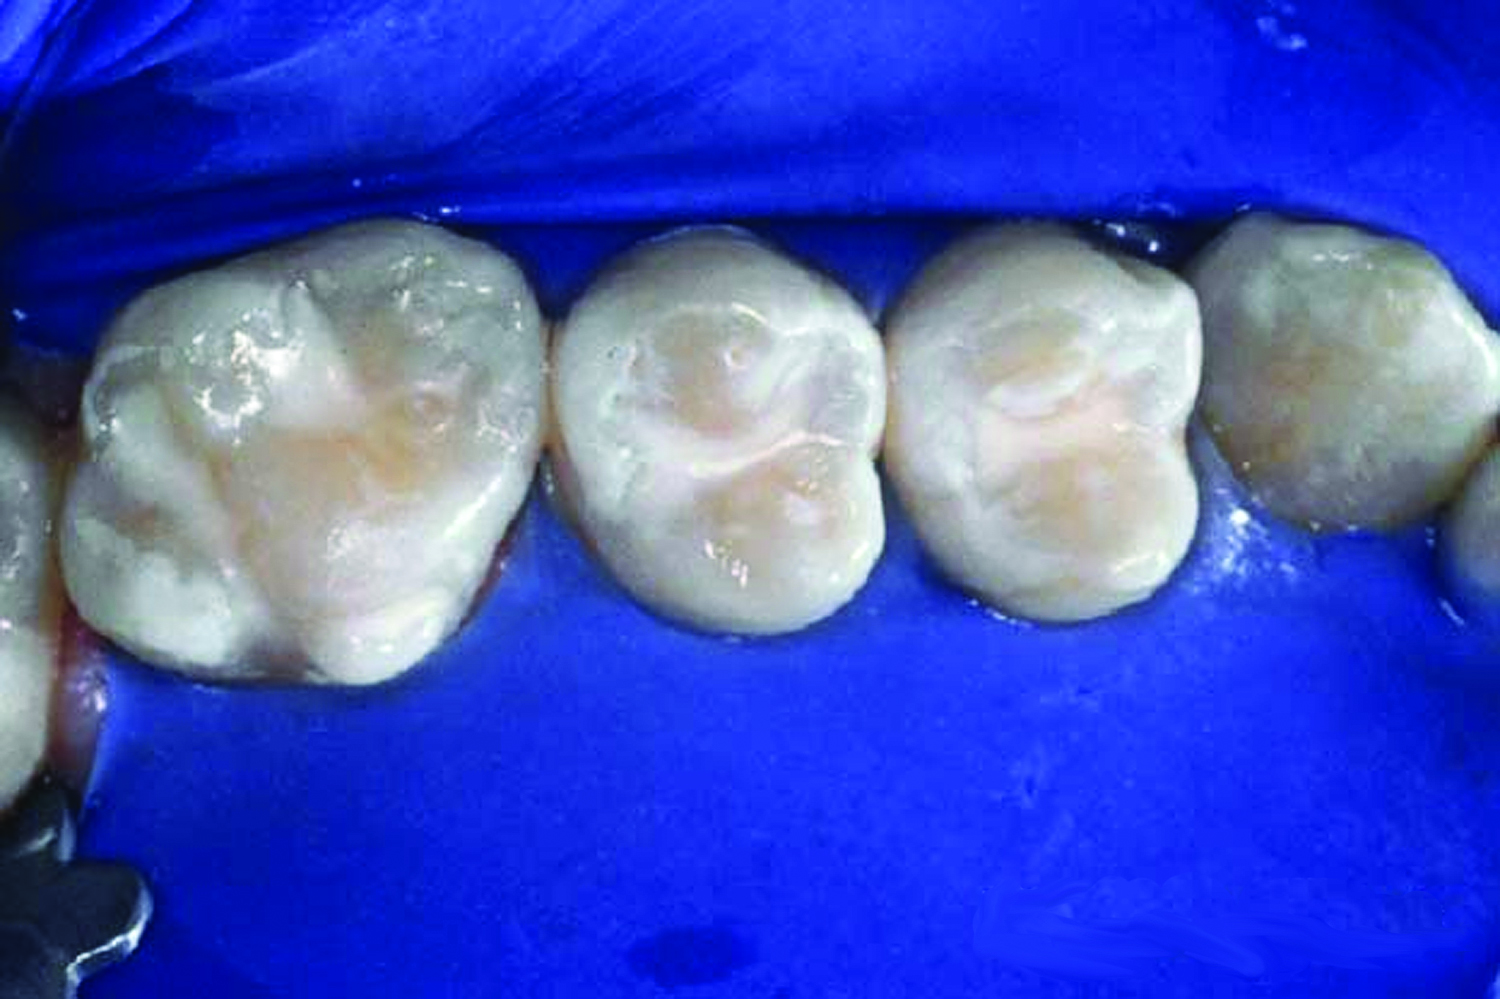

2. Clean the tooth surface with a slurry of pumice and water, a bristle brush with clear water, or an air-powder polisher (Figure 5). Do not use a paste that contains coloring, and/or flavoring agents, glycerin, and/or fluoride, as these may interfere with bonding. Rinse thoroughly with water.

Fig 5. Clean the tooth surface with a slurry of pumice and water, a bristle brush with clear water, or an air-powder polisher.

Figure 5